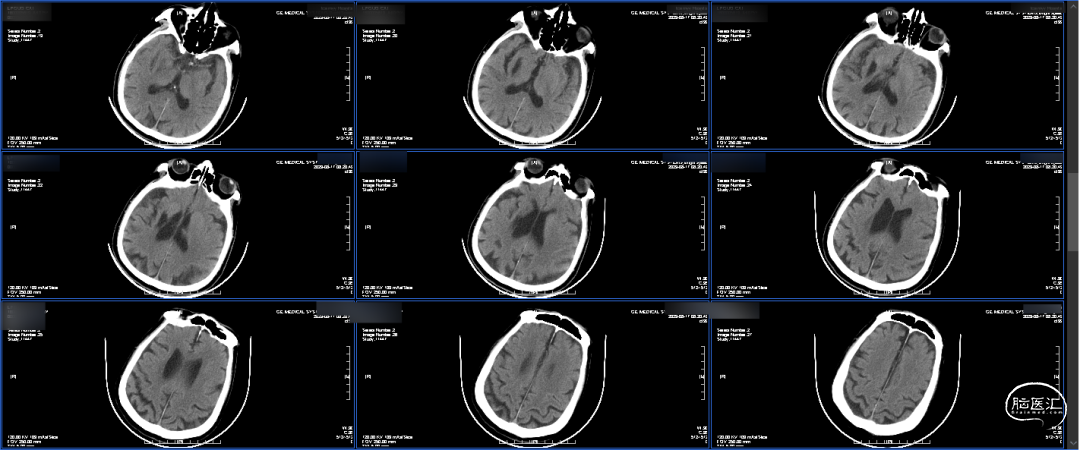

入院急诊头颅CT平扫:右侧基底节区侧脑室旁条索状低密度影,考虑卒中囊,老年性脑改变。

溶栓前CT平扫 :左侧未见确切异常,右侧基底节区为陈旧性脑梗死 。

溶栓后CT平扫:未见出血。